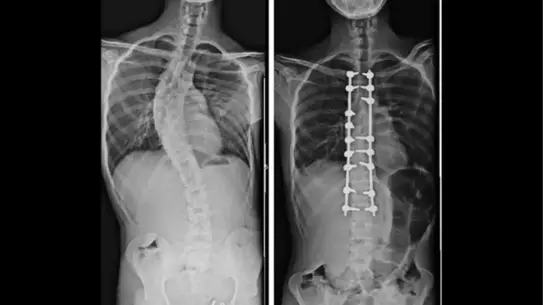

Derin öğrenme algoritmaları, röntgen ve MRI görüntülerini analiz ederek hastalıkların erken teşhisini mümkün kılıyor. Bu sayede cerrahi planlama süreci dakikalar içinde oluşturulabiliyor.

Robotik kollar, milimetrik hassasiyette kesim yaparak komplikasyon riskini azaltıyor. Ayrıca, yapay zeka destekli rehabilitasyon cihazları, hastanın iyileşme sürecini gerçek zamanlı izliyor.